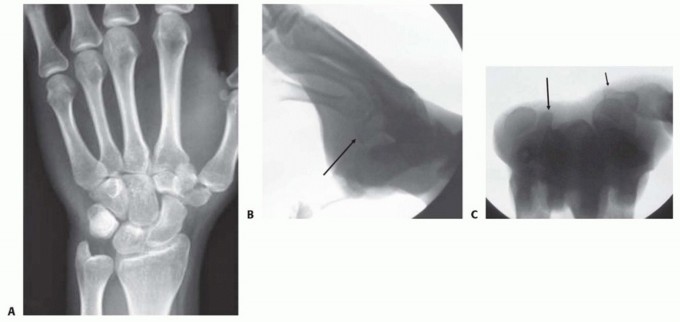

Imaging is the cornerstone of preoperative templating. Routine evaluation begins with high-quality posteroanterior, lateral, and oblique radiographs of the wrist. However, standard views are notoriously inadequate for isolating specific carpal pathology due to osseous overlap. Special radiographic projections are therefore essential. The carpal tunnel view is critical for evaluating the hamate hook and the trapezial ridge. The "papillon view"—a supinated oblique lateral projection with the wrist in radial deviation and the thumb abducted—is highly specific for profiling the hamate hook. Similarly, a 45-degree supinated lateral view optimally visualizes the pisotriquetral articulation.

Despite optimal plain radiography, advanced imaging is frequently required. High-resolution computed tomography (CT) scanning with fine axial, coronal, and sagittal reconstructions has become the gold standard and the imaging modality of choice for complex carpal trauma. CT scans definitively confirm occult fractures, delineate intra-articular comminution, and reveal subtle associated injuries missed on plain films. They allow the surgeon to mentally construct a 3D model of the fracture, facilitating precise preoperative templating of screw trajectories and implant sizes. If dynamic instability is suspected but unconfirmed, an Examination Under Anesthesia (EUA) combined with real-time fluoroscopy (utilizing stress and distraction views) is performed immediately prior to the definitive procedure to finalize the surgical blueprint.

Clinical & Radiographic Imaging Archive